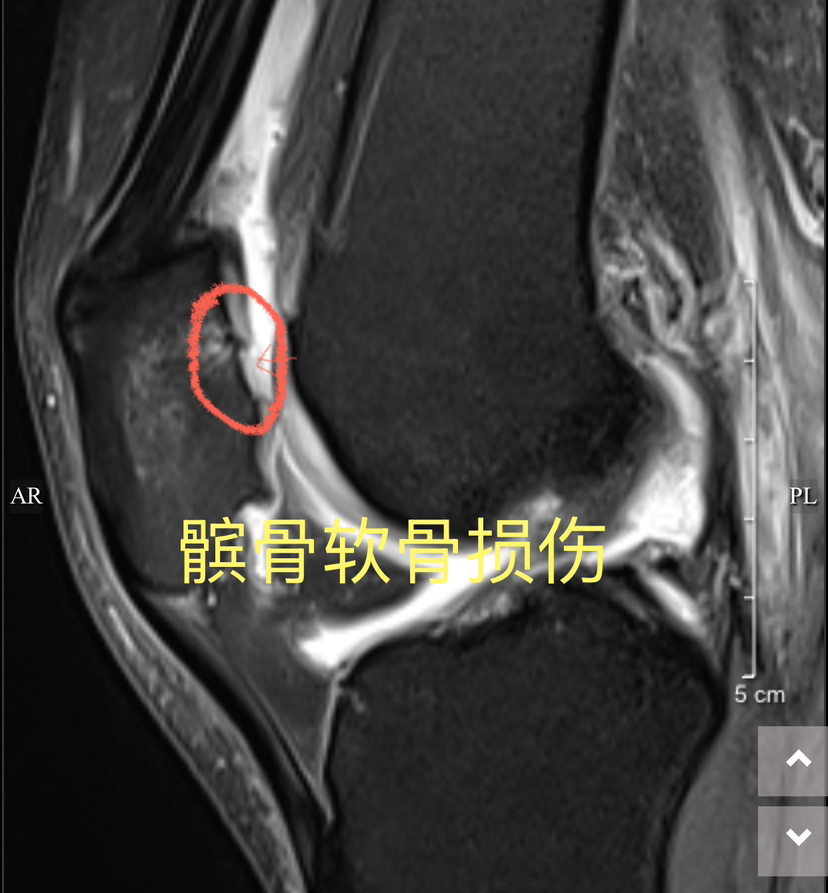

下面展示典型的膝关节软骨损伤,MRI核磁扫描可以清晰发现软骨损伤(3-4度),门诊检查非常常见!